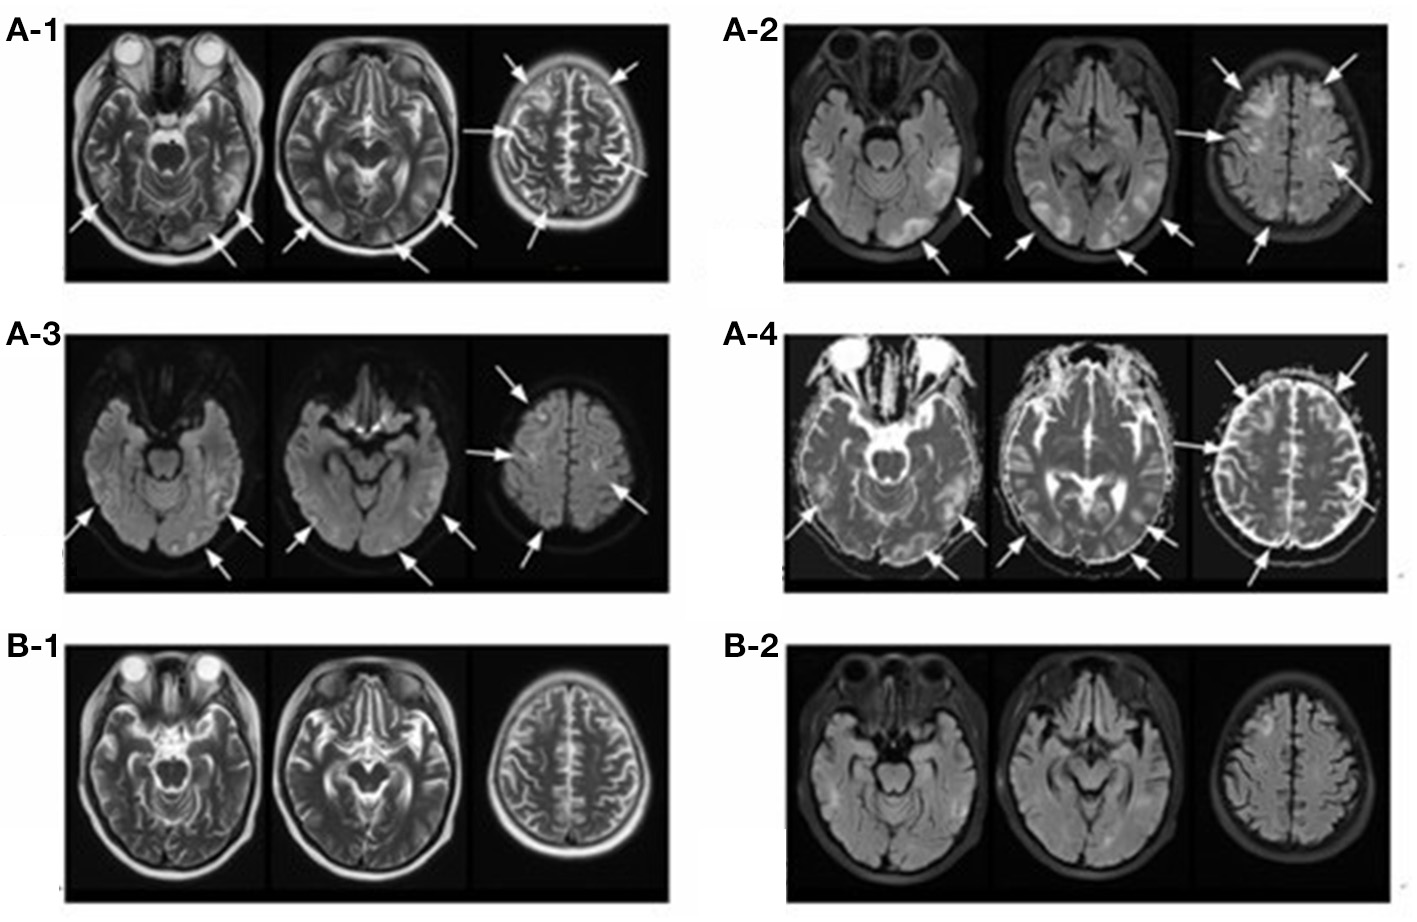

Figure 2

Magnetic resonance imaging (MRI) of brain. T2-weighted (A-1) and FLAIR (A-2) sequences depict hyper-intense lesions involving the bilateral cerebral hemispheres (occipital lobe, parietal lobe, temporal lobe and frontal lobe) and cerebral cortex and subcortex (arrows), most of which disappeared 17 days later (B-1,B-2). Diffusion-weighted magnetic resonance imaging (A-3) and apparent diffusion coefficient (A-4) sequences of the involved regions showed isointense or hyperintensity lesions (arrows).

The follow-up brain MRI after 17 days showed that the degree of gyrus swelling was reduced, most of the abnormal high signal shadows disappeared and multiple small ischemic lesions were found under bilateral frontal-parietal cortex (Figures 2B1,2). Unfortunately, her renal function did not recover with maintenance hemodialysis and oral prednisone gradually tapered after 6 weeks. Her peripheral-blood CD19+ B-cell counts decreased to 1/μl after two times of rituximab infusion and increased to 5/μl six months later when she received another time of rituximab infusion (100 mg) as part of maintenance therapy. She was content with her treatment since the disease was controlled and stabilized. No PRES relapsed and she received a deceased donor kidney transplantation in December 2019. She observed the strict and routine follow-up with treatments to prevent graft rejection, and her renal function and central nervous system condition kept stable until now.